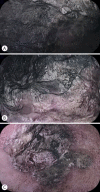

The novel coronavirus disease (COVID-19) quickly spread to all continents. However, data regarding all the signs and symptoms of COVID-19 are insufficient. Patients with COVID-19 might present higher susceptibility to fungal coinfections. Mucormycosis is a rare and often life-threatening fungal disease characterized by vascular invasion by hyphae, resulting in thrombosis and necrosis. This is the first case report of mucormycosis in a COVID-19 patient. An 86-year-old male patient was admitted to the emergency room with acute diarrhea, cough, dyspnea, and fever from 5 days prior. Blood tests revealed a hemoglobin level of 14.3 mg/dL. Five days following the admission, the patient presented with melena and a hemoglobin level of 5.6 mg/dL. A transfusion of three units of red blood cells was required. Esophagogastroduodenoscopy revealed two giant gastric ulcers with necrotic debris and a deep hemorrhagic base without active bleeding. Furthermore, biopsies confirmed mucormycosis. Despite intensive care, the patient died 36 hours after the esophagogastroduodenoscopy.